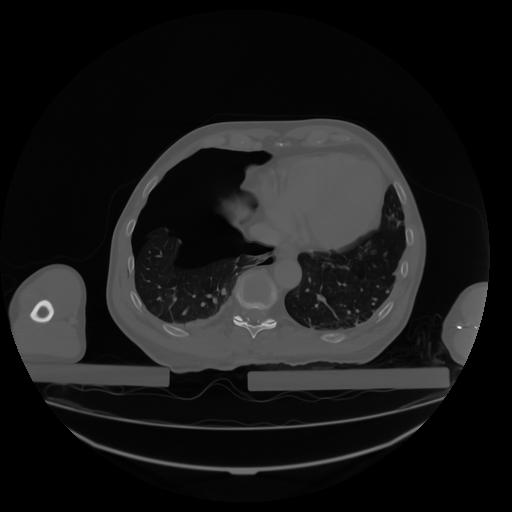

27 CUERPO,CE,Axial,3.0,CUERPO,,